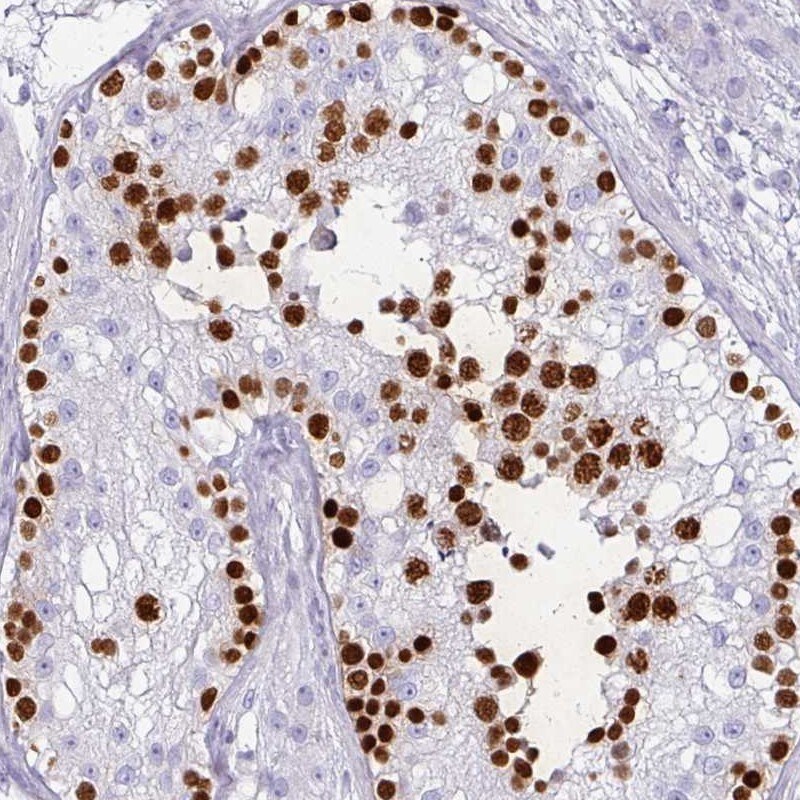

- Immunohistochemical analysis of VCX2 in human testis using VCX2 Polyclonal Antibody (Product # PA5-60787) shows strong nuclear positivity in cells in seminiferous ducts.